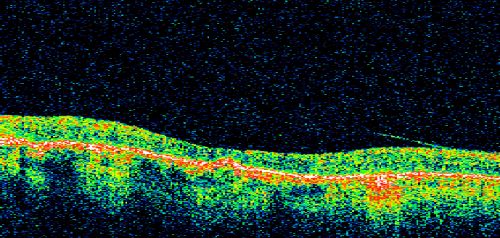

Macular and Peripheral Retinal Scarring from Diabetic Laser Done 25 years previously

72-year-old man had macular and peripheral laser done in the past(1980's)(25 years ago).  His vision, although limited, seems about stable to him.  He is diabetic for 30 years. OD is 20/160, OS  is 20/160.